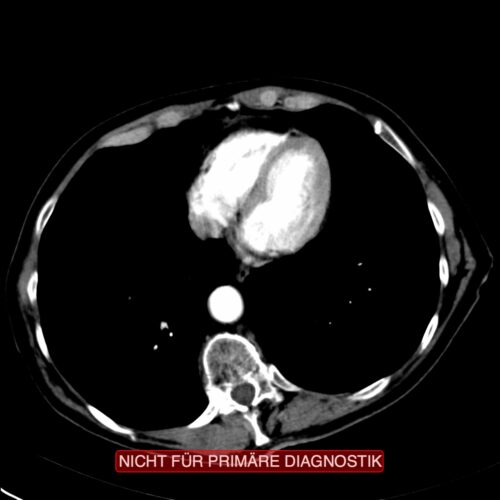

Eine Computertomografie oder MRT dient zur weiteren Abklärung und besserer Darstellung des Tumors und eventueller Fernmetastasen. Zur Frage der Resektabilität wird besonders auf die Infiltration der A. mesenterica superior und der Pfortader geachtet. Fernmetastasen sind eine Kontraindikation für eine Operation. Auch einer ERCP oder MRCP kann nützlich sein, um die Cholestase weiter abzuklären.